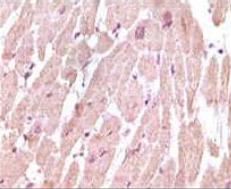

CTnI Mouse Monoclonal antibody[3A10A]

IHC    1/200 - 1/1000